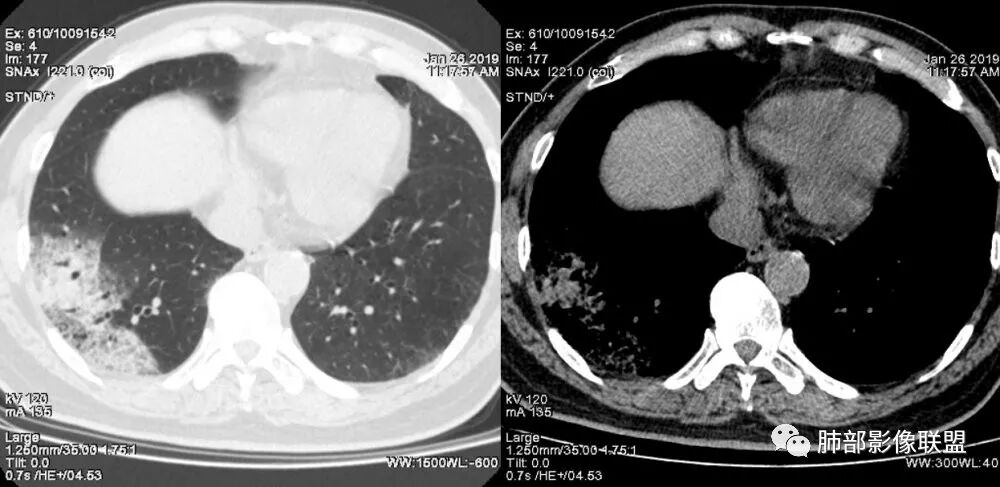

老年女性,右肺下叶沿胸膜下大片状高密度影,外周磨玻璃影,边界较清,内可见蜂窝征及支气管充气征,考虑肺炎型肺癌。

老年女性,咳嗽咳痰病史,右肺下叶大片磨玻璃实变影,胸膜下分布,支气管进入后扩张、僵直,磨玻璃影边界清楚,考虑粘液腺癌。鉴别肺炎。

右肺下叶基底段靠胸膜实变/磨玻璃混杂密度影,边界清楚,内见多发空泡(蜂窝样趋势改变?); 临床:咳嗽咳痰,无发热、胸痛; 考虑腺癌:无发热,感染性病变不首先考虑;部分层面形态类楔形,鉴别肺栓塞

老年女性,右下肺实变影,病灶里有小叶内间质增厚,周围GGo,支气管扩张,粘液性腺癌?淋巴瘤?

中年女性,咳嗽咳痰。右肺下叶片状高密度影,部分实性密度,周围见边界清晰磨玻璃影,内见小空泡,实性区部分支气管堵塞,有重力效应,考虑肺炎型肺癌,建议查痰脱落细胞。

老年人,右肺下叶斑片状阴影,病灶有膨胀性,边缘可见磨玻璃影,其边界清晰,内见僵硬的支气管,部分支气管扩张,首先考虑占位性病变,粘液性腺癌可能。鉴别感染性病变,后者边缘多有收缩性改变或者平直,内部支气管走形自然。

中年女性,右肺下叶沿胸膜下大片状高密度影,实变加GGO,外朝内发展,边界较清,内可见蜂窝征及枯树征,考虑肺炎型肺癌。

右肺病灶,病灶较大,实性+周边ggo,边界清晰,胸膜下分布,长轴平行于胸膜,内部支气管充气征,因不发热,暂不考虑感染性病变,支持肺炎型肺癌。

女性,咳嗽咳痰不发烧,右下外基底段实变影,边缘清楚GGO,有充气支气管征,枯树枝不明显,由外向内;诊断:肺炎型肺腺癌;鉴别:1、肺栓塞(外型神似,但无胸痛丶咯血);2丶肺炎

老年女性,右下肺实变影,糊墙,外朝内发展,病灶里有小叶内间质增厚,周围边界清楚了GGO,支气管扩张明显,考虑粘液癌;不符合点,支气管扩张太厉害了,鉴别淋巴瘤。

患者中年女性,咳嗽咳痰就诊。胸部CT:右肺下叶后基底段片状实变影,由胸膜向内发展呈扇形,病灶里有小叶内间质增厚、蜂窝状影,周围边界清楚GGO,内可见扩张支气管,淋巴结无明显肿大。综合符合粘液腺癌。

老年女性;右下肺混合实变影,呈楔形改变,边缘清晰,支气管进入且扩张,蜂窝状改变,考虑粘膜相关淋巴瘤,鉴别粘液腺癌,肺栓塞。

女,55咳嗽咳痰,右肺下叶片状实变,磨玻璃影及蜂窝影,考虑粘液腺癌。

老年女性,咳嗽、咳痰。右肺下叶沿胸膜下大片状高密度影,外周磨玻璃影,边界较清,小空泡,蜂窝征及支气管充气征,叶间裂串珠征,考虑:肺炎型肺癌,鉴别:肺克,链球菌,NTM等感染。

右肺下叶大片状影,密度不均匀,部分实变部分磨玻璃,大部分病灶尚清晰,其内支气管稍扩张,中年女性,首先考虑粘液腺癌,待鉴别淋巴瘤,常规抗炎治疗后复查。

中年女性,右肺下叶实变,近似扇形,外朝内发展趋势,外围紧贴胸膜面,中心密度略高,边缘密度略低,病灶内支气管略扩张。考虑肺炎型肺癌。常规建议抗炎治疗后复查,如无变化或变化不明显,建议穿刺活检。

胸膜下,实变,毛玻璃影,囊,边界清,枯枝,粘液腺。

老年女性,右肺下叶大片实变,小叶间隔及小叶内间隔增厚,边界较清,其内支气管似乎可见稍扭曲,分支减少。考虑1.肺炎型肺癌2.结合临床除外类脂性肺炎。

起源于胸膜下,实性成分,边缘Ggo,边界清晰,内可见小叶间隔增厚,粘液腺癌可能。建议先消炎后复查。

右肺下叶胸膜下大片状MGGO,其内结构紊乱,可见空泡征,病灶内近端支气管扩张,远端闭塞,形态不规则,边界部分清楚,部分似清非清,考虑粘液腺癌,鉴别淋巴瘤

该病灶主病灶位于胸膜下(肋膈角处),边缘膨隆改变,周围毛玻璃,边界清楚,病灶内支气管僵直,轻度扩张,小分支无,符合枯树枝改变,有多发小空泡(难与支气管区别),应该符合肺炎性肺癌,但无蜂窝,没有增强无法判断有无粘液、血管特点,如果周围显示的空泡是支气管,其已达到远端,这些有符合炎性特点,工作中,我会先抗炎膨后复查再定。

这是潘老师说的外向内吗?右下实变,蜂窝,GGO,支气管变形迂曲,局部膨胀感,肺炎性肺癌,粘液腺癌可能。常规先抗炎再复查。鉴别淋巴瘤,淋巴瘤支气管一般不变形,壁光整,病程长。

1.本例病灶较大片混杂密度影,胸膜下分布为主(未沿着支气管分布),该分布特点可见于大叶性肺炎、干酪性肺炎、淋巴瘤及粘液腺癌等。可惜未提供增强扫描图像。

2.病灶示中央实变区,周围GGO,可见明显小叶间隔增厚,GGO边界清楚,应当考虑到恶性病变的可能性。肺炎因炎性水肿及渗出,影像上边界常模糊不清,注意早期粘液腺癌可出现似清非清的边界。粘液腺癌因粘液成份较多,密度一般偏低,纵隔窗病灶常会消隐或范围会明显缩小,这不同于炎性实变。

3.病灶内支气管走形略显僵直,侧支少(粘液阻塞),也符合肺腺癌的枯树枝征。而大叶性肺炎的支气管是管壁光整、通畅、自然,结核的支气管常常壁增厚,甚至狭窄后扩张;

4.患者临床症状不重,临床炎性指标不高,结合肺内影像,应警惕肺炎型肺癌。